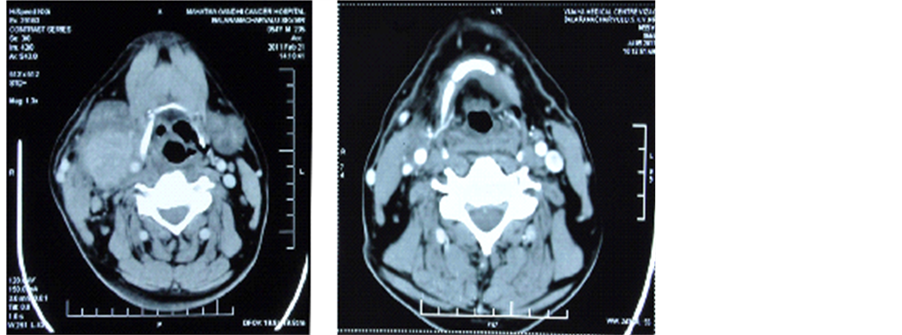

The patient was followed up for 24 months; CT scan displayed a good response to combination of radiation with cisplatin and nimotuzumab (Figure 1).

21st Feb 2011 5th July 2011

Figure 1. (a) Pretreatment―CECT of neck showing right upper cervical lymph node measuring 5 cm × 4 cm with central necrosis; (b) Post treatment―CECT of neck showing very minimal enhancing lesion in the right side of neck. Post CT & RT, the residual disease measures 1 cm × 0.7 cm.